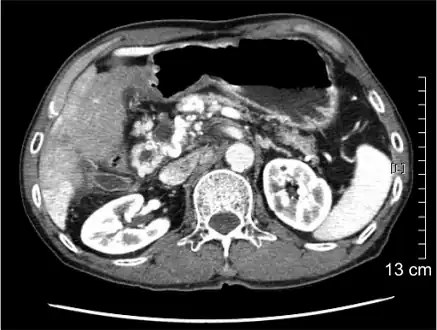

Portal vein thrombosis seen with computed tomography.

The diagnosis of portal vein thrombosis is usually made with imaging confirming a clot in the portal vein; ultrasound is the least invasive method and the addition of Doppler technique shows a filling defect in blood flow. PVT may be classified as either occlusive or nonocclusive based on evidence of blood flow around the clot.[5] An alternative characterization based on site can be made: Type 1 is limited to the main portal vein, Type 2 involves only a portal vein branch (2a, or 2b if both branches are affected), and Type 3 if clot is found throughout both areas.[8] Determination of condition severity may be derived via computed tomography (CT) with contrast, magnetic resonance imaging (MRI), or MR angiography (MRA). Those with chronic PVT may undergo upper endoscopy (esophagogastroduodenoscopy, EGD) to evaluate the presence of concurrent dilated veins (varices) in the stomach or esophagus.[3] Other than perhaps slightly elevated transaminases, laboratory tests to evaluate liver function are typically normal.[1] D-dimer levels in the blood may be elevated as a result of fibrin breakdown.